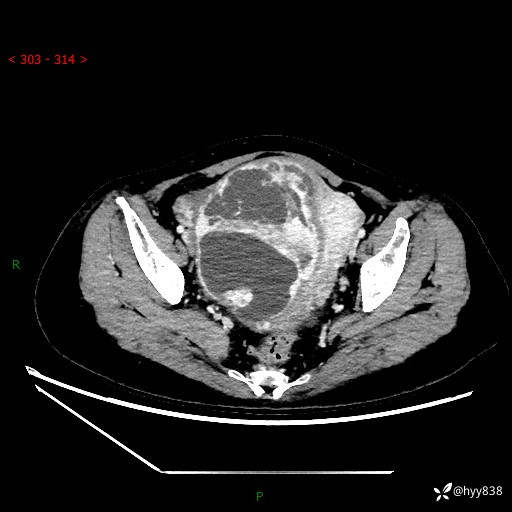

辅助检查:CT

盆腔CT平扫

增强(动脉期+静脉期)